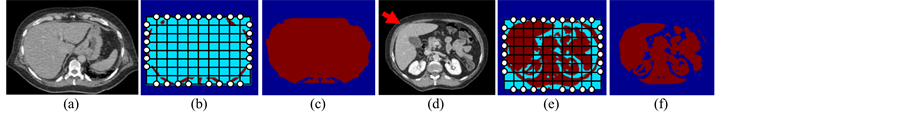

To exclude all information outside the ribcage, we create a mask region for each axial image by performing the following procedures. First, a median filter is used to reduce noise. Then, a two-stage multi-thresholding Otsu’s (TSMO) method [17] improved by our proposed range constraint is applied to a filtered image. The result of the thresholding presents five segments containing background, three levels of soft tissues, and hard-tissue regions. Next, the hard-tissue regions represent ribs and vertebrae, and a template of seed points is created to cover these regions (see Figure 4). Subsequently, we move these seed points to boundaries of hard-tissue regions, and use straight lines to connect these points together in order to generate a mask region. However, regions of ribs and vertebrae are not always clearly displayed in some axial images (see a red arrow in Figure 4). Thus, we use a combination of soft-tissue regions instead of hard-tissue regions. In fact, this combined region is often larger than a boundary of the ribcage. Therefore, morphological erosion is required to shrink this combined region after connecting all seed points together.

Figure 4. An example of mask-region creation. (a) and (d) Two sample images, (b) and (e) templates of seed points, (c) and (f) mask regions.